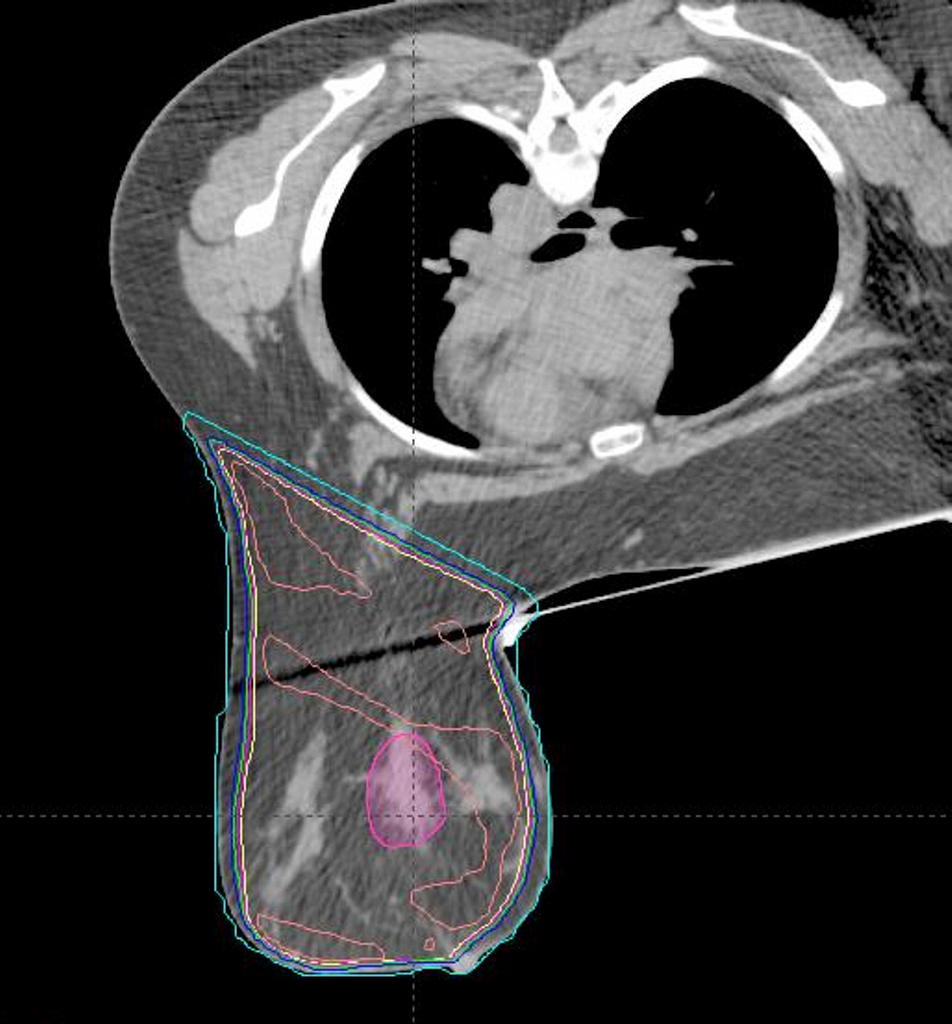

Arguably, every IMRT LCD/LCA in America (the 3 LCD/LCAs cover about 20 states and D.C.) supports IMRT for any/all right breast cancers. I say this because 1) "breast" is in the thorax chapter of every med school anatomy textbook, 2) breast radiotherapy is, evidently, thoracic radiotherapy (see below), and 3) all the IMRT LCDs say IMRT is necessary for thoracic malignancies, and all the LCAs list right breast ICD-10s as supporting necessity too.

Is this a course of radiation for a "thoracic malignancy"? I don't think we should nudge payors to cover breast IMRT as their default option. IMRT for breast Ca should be an exception.